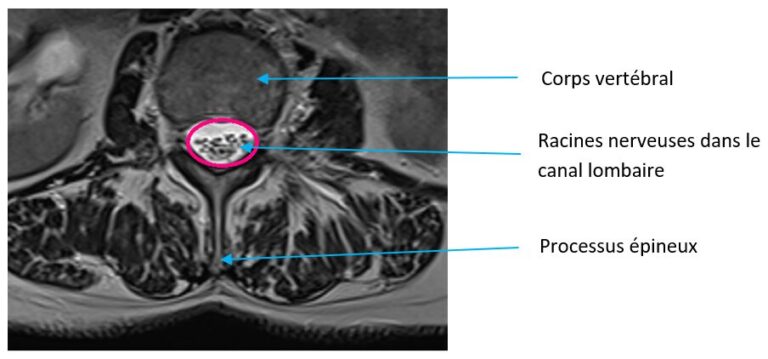

La colonne vertébrale est constituée de vertèbres au milieu desquelles passe le canal rachidien. Celui-ci contient, au sein d’une enveloppe que l’on appelle « sac dural », la moelle épinière et les racines nerveuses. Selon la constitution du patient ou lors d’usure naturelle (arthrose), un rétrécissement du canal rachidien peut survenir.

Canal Lombaire étroit